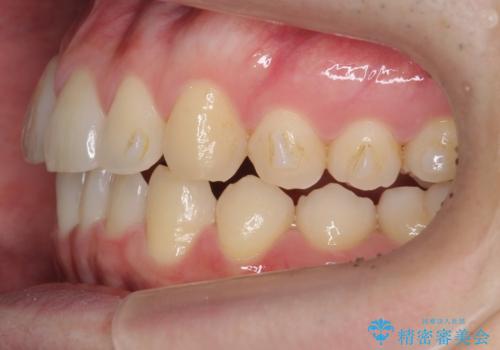

- 右上の前歯が内側に入っているのを気にして来院。

右上の奥歯を後ろに移動して、前に出すスペースを確保してから並べました。

奥歯を後ろに送るために、矯正用インプラントを使用しています。

前歯が内側に入っていると、笑った時にそこが黒くなり、歯が抜けたように見えます。

口を開けたとき、笑顔の印象が大きく変わり、大変喜んでいただけました。